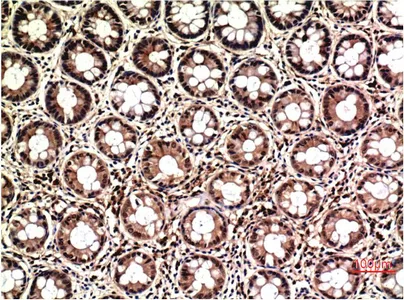

CK7(12D7)Mouse Monoclonal Antibody

Cat: AMM08857

Size1:50μl Price1:$128

Size2:100μl Price2:$230

Size3:500μl Price3:$980

Size2:100μl Price2:$230

Size3:500μl Price3:$980